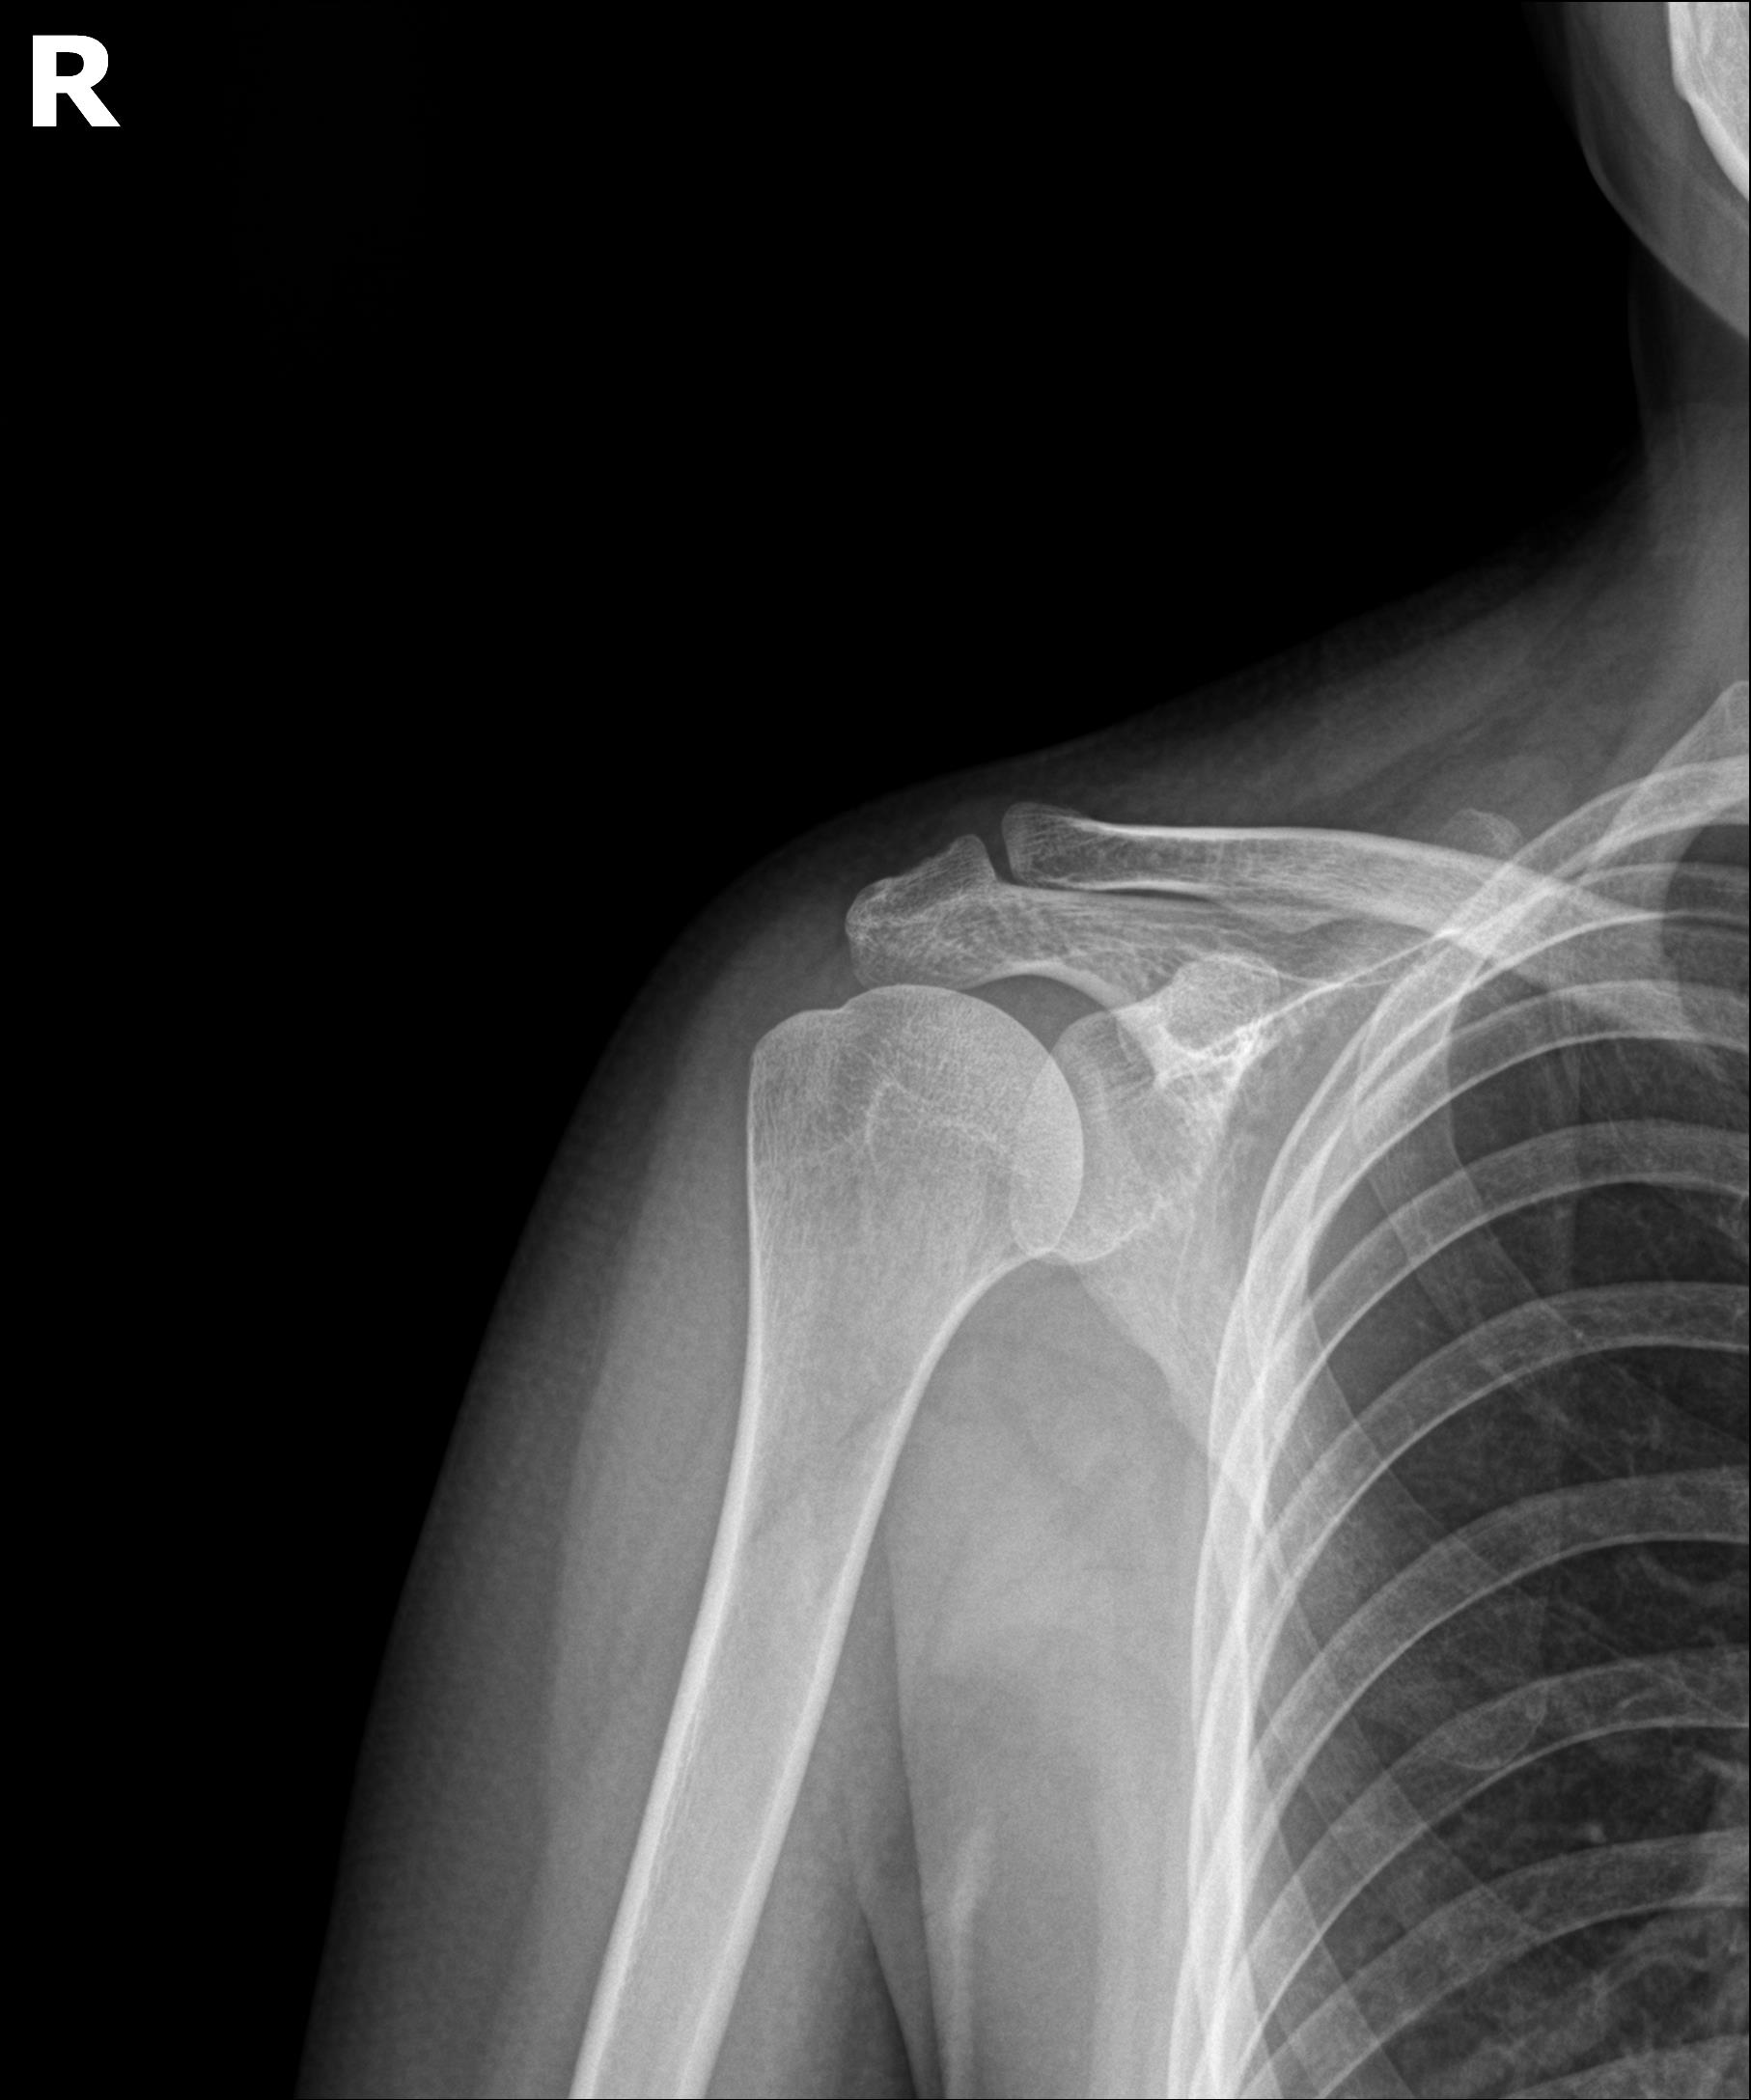

케이스 3: 흡수기 대형 석회 (1회 제거)

환자: 30대 여성, 임신 5개월, 양측 어깨 통증

특이사항:

임신 중이라 X-ray, 전신마취 불가

참을 수 없는 통증으로 시술 결정

시술:

국소마취 하 분쇄흡입술

1.6cm 흡수기 석회 1회 제거

타 병원 실패 후 내원 케이스